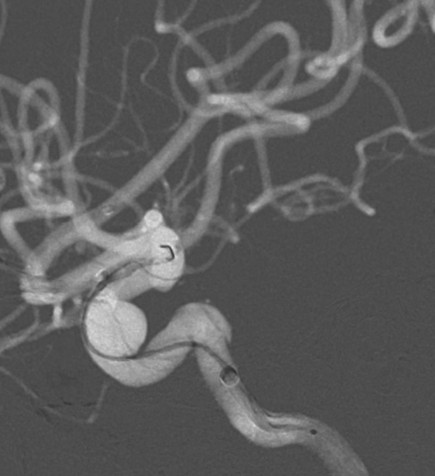

术前造影:

正侧位造影示动脉瘤内造影剂明显滞留,载瘤动脉通畅,血流导向作用显著。

术后即刻: